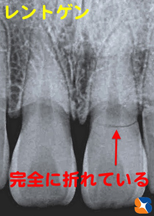

Dr「前歯が深い位置で完全に折れています。私も95%抜歯だと思います。

Dr「前歯が深い位置で完全に折れています。私も95%抜歯だと思います。